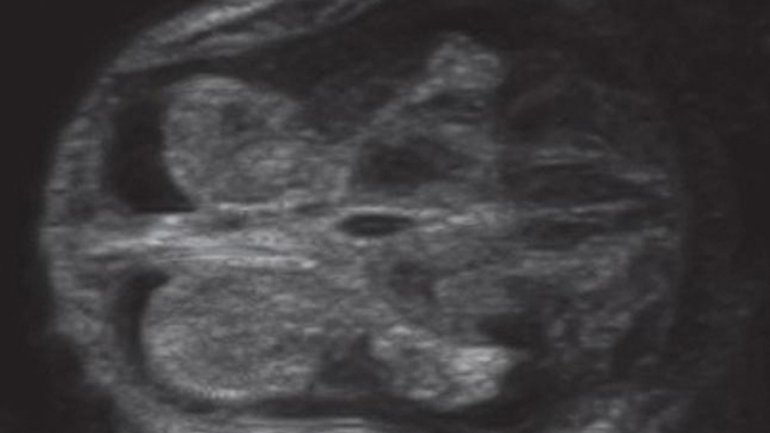

Ultraschall 12. SSW

Auf dem Ultraschallbild sieht man den Kopf und einen Teil des Oberkörpers. Im Kopf sieht man die Schädelknochen und die Anlagen von Kiefer und Zähnen, im Oberkörper den Knochen des Schlüsselbeins. Auch die kleine Nase und der Mund sind gut zu erkennen – und das, obwohl der Fötus nur fünf Zentimeter misst.